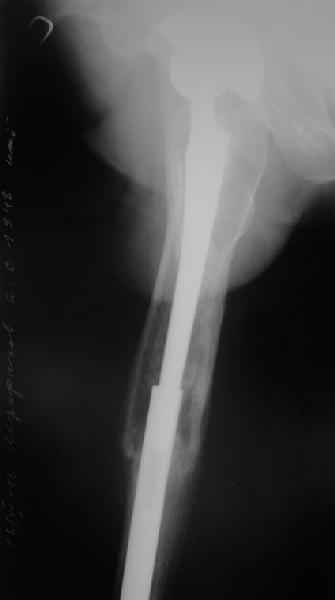

Re: Перипротезный перелом

Перелом бедра сросся. Конечность опорная и безболезненная, ходит без трости. Ножка, похоже, реинтегрировалась, как и надеялись. Снимки и фото в приложении. Комментарии приветствуются.

Надо ли что-то делать дальше, как полагаете? Убрать винты? Убрать "удлинитель ножки"? Или оставить все, как есть? Спасибо заранее.